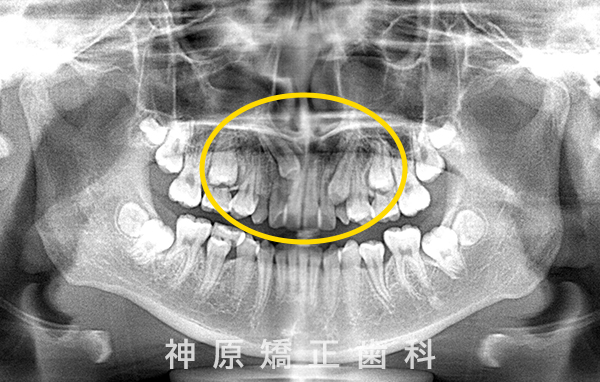

開窓牽引開始時

上のあご(上顎)の右側の犬歯について、歯の生えてくる方向に異常が見られました。そのため、歯ぐきを一部開いて、犬歯を正しい位置に引っ張り出す「開窓牽引」という処置を行いました。